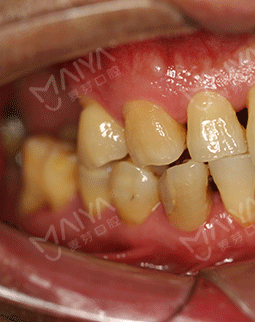

由于职业原因,特别爱好摄影和旅游。去年年底到今年6月,和朋友们分别去了南极和北极,我把这次南北极之旅称之为“南征北战”。尽管今年已经58岁了,热爱冒险又健谈的我和同龄人相比起来却像一个40多岁的人。但由于年轻时对口腔保护意识的薄弱,导致了现在口内5颗牙缺失,大家都想不到吧?别人是缺前牙,我是缺大牙,这大牙可是咀嚼食物的主要牙齿,所以我很多时候吃饭都是囫囵吞枣,对饮食生活造成了相当大的困扰。吃东西费劲,很多时候朋友邀约出去聚会,却只能眼睁睁的看着大家享受美食。随着年龄的增长,缺牙造成的营养吸收不均衡,在饮食和身体健康上带给我的是双重困扰。有人劝我镶牙,但活动牙我看不上,固定牙又不适合伤害健康的牙齿,思前想后,还是决定种牙。

2017年7月 口腔保健意识差,导致我口内5颗牙缺失

由于职业原因,特别爱好摄影和旅游。去年年底到今年6月,和朋友们分别去了南极和北极,我把这次南北极之旅称之为“南征北战”。尽管今年已经58岁了,热爱冒险又健谈的我和同龄人相比起来却像一个40多岁的人。但由于年轻时对口腔保护意识的薄弱,导致了现在口内5颗牙缺失,对饮食生活造成了相当大的困扰。吃东西费劲,很多时候朋友邀约出去聚会,却只能眼睁睁的看着大家享受美食。随着年龄的增长,缺牙造成的营养吸收不均衡,在饮食和身体健康上带给我的是双重困扰。

我虽然走遍大江南北,也看遍了大江南北的风光。这本是羡煞旁人的事,但对我来说,却有许多遗憾。20年前牙齿就开始脱落了,但当时科学、技术都没有达到现在的标准,自己也没有太在意,如今随着生活品质的提升,科学、技术的提高,对恢复牙齿的需求也变得越来越迫切。